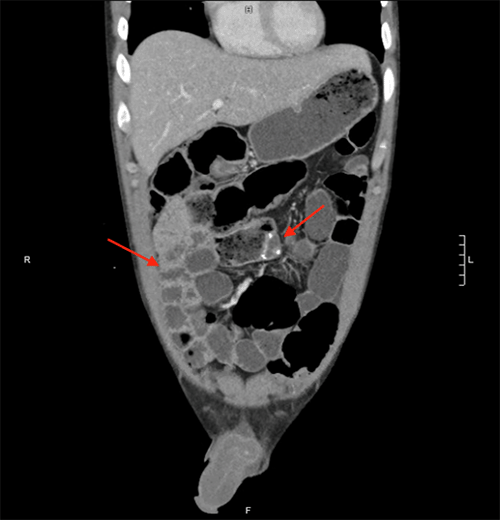

The patient presented with abdominal pain, diarrhea, vomiting, and oral intolerance and was admitted for presumed Crohn's flare with concern for possible stricture. He was started on intravenous steroids and underwent video capsule endoscopy, demonstrating inflammation and ulceration in the small intestine without stricture. However, his symptoms did not improve with IV steroids. After two weeks in the hospital, the patient had a sudden increase in abdominal pain and distension with worsening leukocytosis. The CT scan demonstrated dilated loops of small bowel in the left abdomen and decompressed loops in the right side of the abdomen, lateral to the colon, with a swirling of mesenteric vessels, indicative of an internal hernia with low-grade obstruction (Figure 2 and Figure 3).

Figure 3. CT Scan Demonstrating Duodenojejunostomy in Prior Orientation in Right Upper Quadrant (Upper Arrow) and Partial Mesenteric Swirl (Lower Arrow). Published with Permission